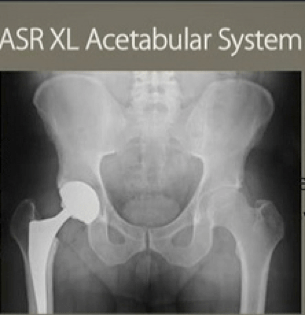

After nearly 1300 complaints since November last year with the Food and Drug Administration (FDA), the DePuy Pinnacle may be facing the same fate with his brother ASR Hip Implant – a product recall. Most of the reports are about an unexplainable hip pain, possibly suggesting metallosis on the hip area. While proves to be a less invasive and less burdensome procedure, there are some conditions where a hip replacement is the only option.

Metallosis is a medical condition due to the collection of metal particles in the soft tissues of the body. This is a very typical complication due to the presence of a metal-on-metal device inside a person’s body. Device like a defective DePuy Pinnacle Hip Replacement might put you at such situation when it is installed in your system. The friction produced by the rubbing of the 2 metal components of this device cast off tiny bits of metallic substance As these bits of metal ions collect on the nearby tissues, the body is then activated. The body’s reaction, particularly the immune system, has been theorized to cause the inflammation of the surrounding tissue.

The manifestations of metallosis may also suggest other concerns such as fracture of the surrounding bones of the implant or the dislocation of the components of the implant. Unfortunately, metallosis might predispose you to more adverse effects. Like in the case of too much cobalt and/or chromium levels in the blood which could result in critical neurological illnesses or more seriously cancer.

The only treatment to prevent further sloughing or metallic ions to the body is the revision surgery. The problem, however, the extent of damage on the surrounding tissue due to metallosis might reduce the chances of a successful revision surgery. Thus early detection and correction of the problem is necessary to avoid the more unfavorable events to occur. Even the slightest symptom may need doctor’s attention. Moreover, for legal concerns, a lawsuit may be filed if you have strong grounds that you have sustained harm from the use of this product.